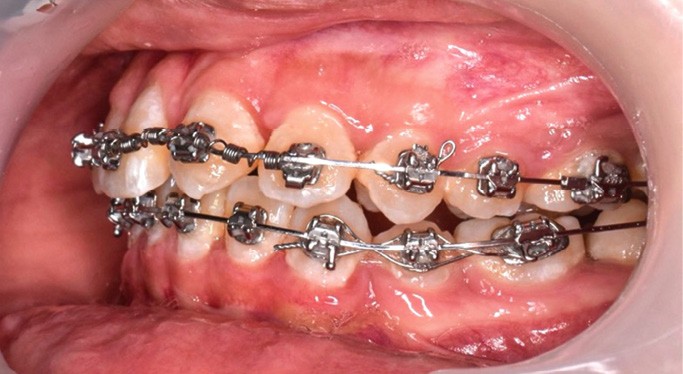

L’objectif du traitement est la correction de la DDA tout en assurant le remplacement de la 21 compromise. Décision a été prise d’extraire 34 et 44, ainsi que 21 et 14. La traction de la 23 a été réalisée à l’aide de forces légères, sur un arc transpalatin (fig. 9). Le nivellement et l’alignement, puis une mécanique par glissement ont permis d’aménager l’espace suffisant à la stratification de la canine. Elle associait un ressort en nickel-titane à des élastiques de Classe II (4 ½ oz, 3/16’’) sur un arc en acier .019×.025. Une phase d’ingression a été réalisée pour ajuster le niveau du bord libre de la canine à celui de l’incisive controlatérale (fig. 10-12).

Les corrections esthétique et fonctionnelle de la canine ont été effectuées par stratifications de résine composite (fig. 13). Au préalable, une simulation numérique de la nouvelle forme à donner à la canine a été élaborée. Une fois imprimée, cette simulation a servi à fabriquer une clé en silicone moulant les faces palatines des incisives. Cette clé a été garnie d’une fine couche composite de masse « émail » (Miris, ColteneR, Suisse) qui a été polymérisée une fois replacée en bouche pour constituer une coquille palatine. Afin d’élargir légèrement le profil d’émergence, des matrices (Slick Bands Margin Elevation, Garison, R USA) ont été insérées dans le sulcus des faces proximales avant d’y fouler une fine couche de composite. La coquille a ensuite été remplie de différentes masses de composite « dentine ». Une dernière fine couche de composite de masse « émail » a finalement été appliquée en surface avant de procéder au polissage et aux finitions. Après contrôle des axes, la fermeture réciproque des espaces d’extraction s’est poursuivie. Cette phase a été suivie par les finitions, puis la dépose. Des fils collés au maxillaire et à la mandibule assurent la contention, complétés par une gouttière thermoformée maxillaire (fig. 14-20).